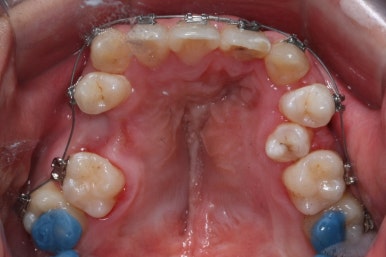

부산구순구개열 키다리아저씨치과에 처음 오셨을 때의 입 안의 모습입니다.

입천장이 갈라져서 어릴 때 봉합 수술을 했기 때문에 그 상처가 굵게 남아있는 것을 볼 수 있습니다. 일반적으로 피부상처도 다른 부위보다 단단하듯이 입천장의 봉합 상처도 매우 단단하게 아물기 때문에 성장에 방해를 주게 됩니다.

가로폭이 매우 좁고 찌그러져 있습니다.

또한 위턱이 앞으로 자라나는 것도 방해해 대부분 앞니가 거꾸로 물리게 됩니다.

또한 가랄져 있던 선에 걸쳐 있는 영구치 일부는 선천결손이 되는 경우가 많습니다.

이번 환자분도 이런 특징을 모두 갖고 계셨습니다.